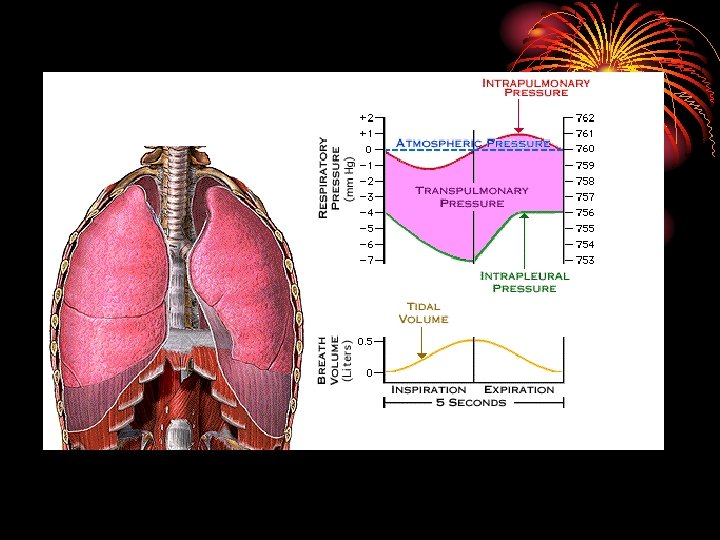

2. External intercostal muscles: anteroposterior diameter, 10% only. 3. Accessory inspiratory muscles: act in forcible respiration: scalene and sternocleidomastoid muscles. Mecahnics Contraction of insp. muscles decreases intrapleural pressure from – 2. 5 mm Hg to – 6 mm. Hg : by increasing the thoracic cavity the lungs will move with the thoracic cage as the parietal and visceral pleurae are in contact, the pressure in airways decreases, leading to entry of air from outside.

• In forcible insp. intrapleural pressure reaches – 30 mm Hg Expiration: • Passive process due to elastic recoil of insp. muscle and lungs leading to increased press. in airways and outflow of air. • Accessory expiratory muscles work in forced expiration: abdominal muscles and internal intercostal.

Summary • Inspiration is an active process due to contraction of respiratory muscles: diaphragm & external intercostal muscles. • Intapleural pressure at end of quiet expiration is -2. 5 mm. Hg and goes down to 6 during inspiration. • V/Q is normally 0. 8 • Compliance of the lung is the change in volume due to the change in pressure.